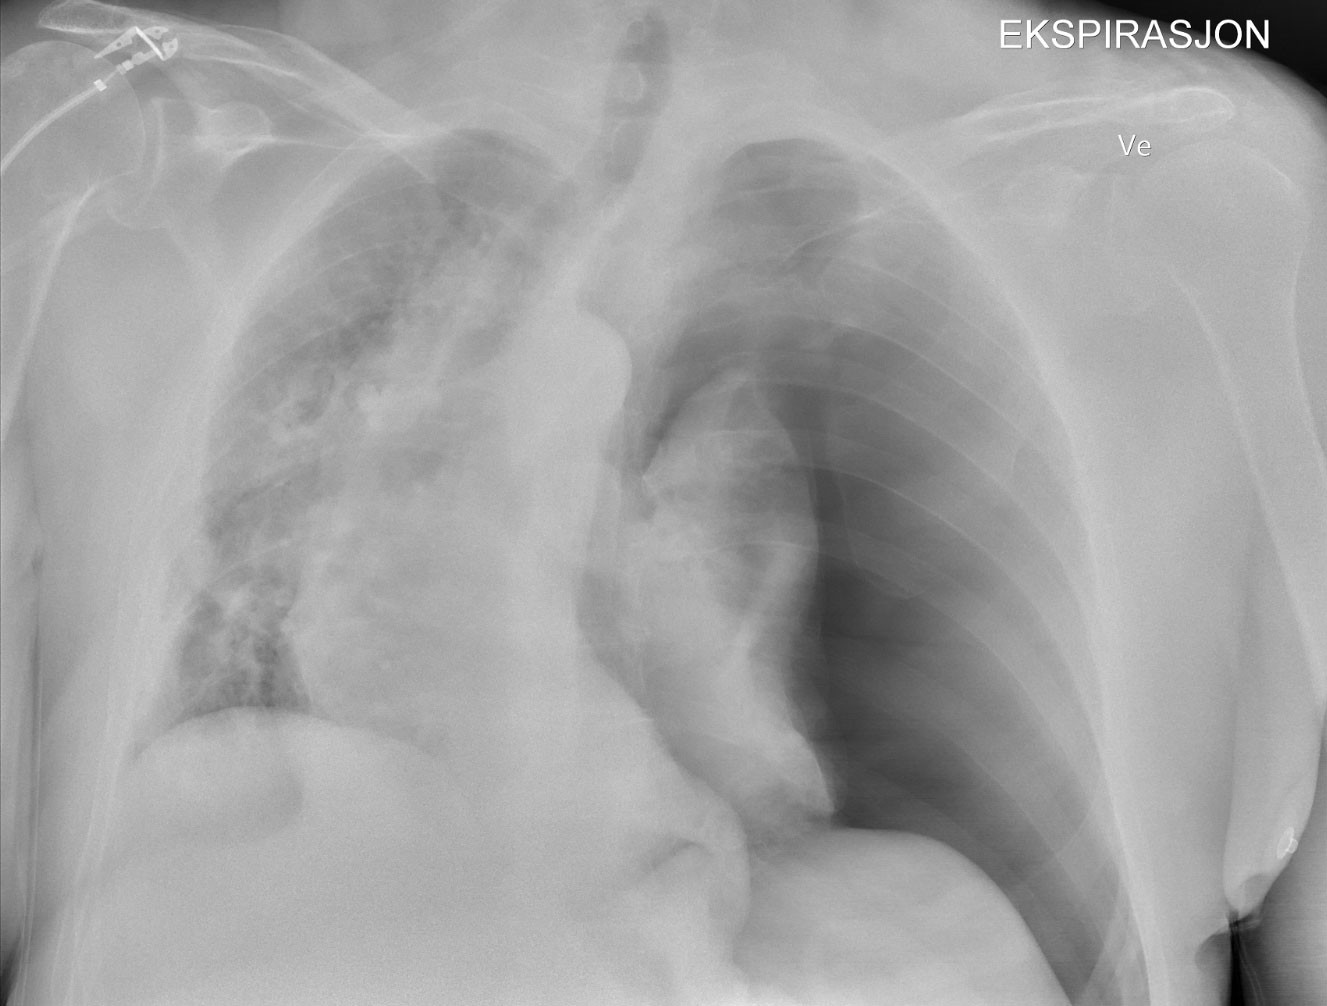

En time før operasjonsslutt falt oksygenmetningen til 89 %, tidevolumet fra 550 ml til 366 ml og middelblodtrykket fra 70 mmHg til 60 mmHg. Oksygen i inspirasjonsluft ble økt fra 40 % til 100 %, og inspiratorisk overtrykk ble økt fra 9 cm til 18 cm vann. Oksygenmetningen steg til 91 %, blodtrykket endret seg ikke. Det ble ikke lyttet på lunger eller tatt blodgass. Operasjonen ble fullført, narkosen stoppet og larynksmasken fjernet uten problemer. Ved ankomst på postoperativ avdeling var oksygenmetningen 88 % til tross for påsatt oksygenmaske med 100 % oksygen. Pasienten var tungpustet, klam og blek med blodtrykk 90/60 mmHg. Vakthavende anestesilege ble tilkalt med en gang og oppdaget med ultralyd etter få minutter manglende lungeglidning (lung sliding) av pleurabladene på venstre side. Røntgen thorax bekreftet venstresidig overtrykkspneumothorax (figur 1).

Kirurg anla i lokalanestesi et 12 French Portex-dren i femte interkostalrom på operasjonsavdelingen 1,5 time etter skulderoperasjonen. Lungen reekspanderte etter to timer med 5 mmHg sug. På intensivavdelingen tre timer etter skulderoperasjonen hadde pasienten behov for smertestillende medikamenter, men blodtrykket var normalisert og oksygentilførselen trappet ned fra 6 L til 2 L på brillekateter. Thoraxdrenet ble fjernet etter 15 timer og pasienten utskrevet 24 timer etter skulderoperasjonen. Ved oppfølging seks måneder etter var han symptomfri og aktiv.